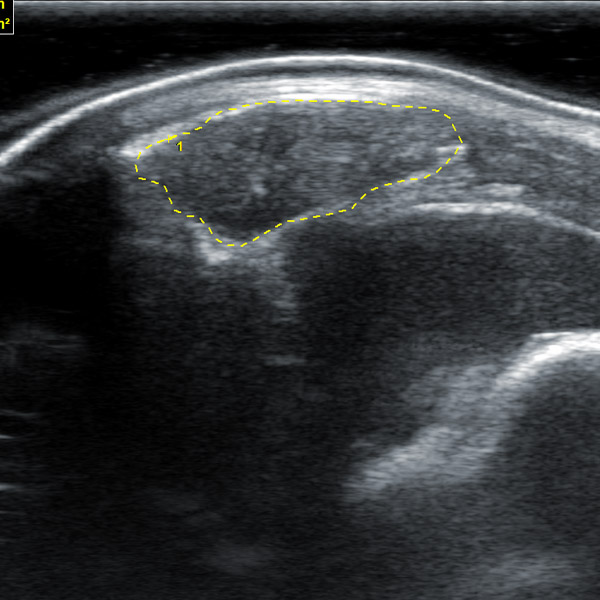

1.23. Built-in professional back fat eye muscle storage image system, can store back fat eye muscle images according to different parts of different animals for inspection

1.30. Image editing: Stored images can be edited. Stored videos can be edited for each frame

1.31. When measuring animal back fat, the back fat measurement and eye muscle depth can be adjusted to be on the same line

2. Animal back fat eye muscle probe:

2.1. Frequency: 2.5-6MHz 18cm long linear array probe

IV. Features of animal backfat eye muscle probe:

1. 18cm long professionally designed backfat eye muscle probe, which can fully test the backfat eye muscles of various animals

2. The probe scanning depth can reach 30cm, which can well present the eye muscles of large animals

3. High-frequency probe and high-quality Doppler color ultrasound images can well identify the measured muscle quality grade